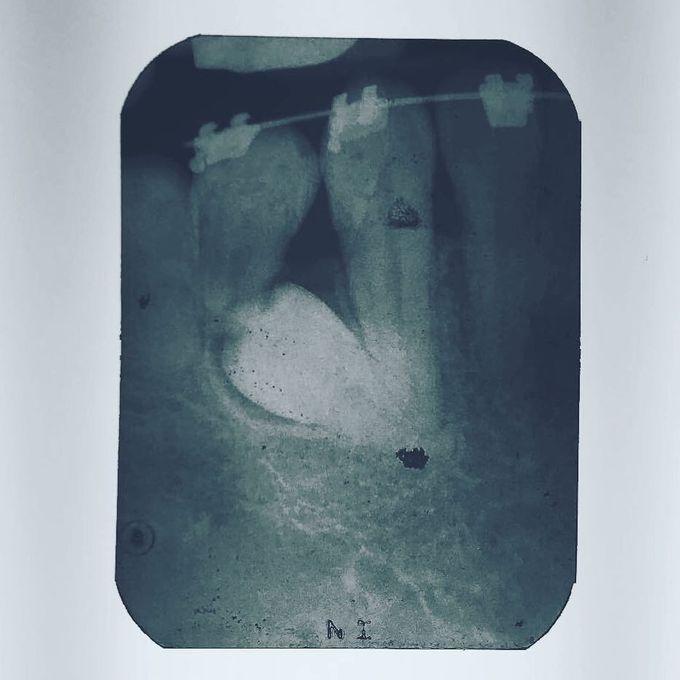

¿Dientes supernumerarios? Bueno cuando hablamos de dientes supernumerarios nos referimos a las piezas dentales adicionales a la cantidad normal que debería tener una persona (Dentición temporal = 20 y Dentición permanente= 32), por lo que si tenemos más de esta cantidad estamos hablando de supernumerarios. Los dientes supernumerarios también conocidos como hiperdoncia o desarrollo de dientes extras, se ha mostrado mayor incidencia en los hombres. Los dientes supernumerarios son anomalías en el desarrollo dental que pueden estar o no asociadas a algún síndrome. Su diagnóstico se realiza mediante un estudio radiológico (radiografía panorámica). Los dientes supernumerarios tienen una morfología variada, pueden ser dismórficos o cónicos, eumórficos o suplementarios; son una duplicación de los dientes de la serie normal y molariforme que suelen presentar una forma molar irregular. Después del diagnóstico radiológico de los dientes supernumerarios se procede a realizar el tratamiento quirúrgico para retirar la pieza ya que esta podria comprometer piezas adyacentes.